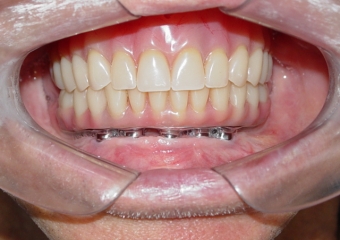

Prótese fixa em resina

Sorriso final